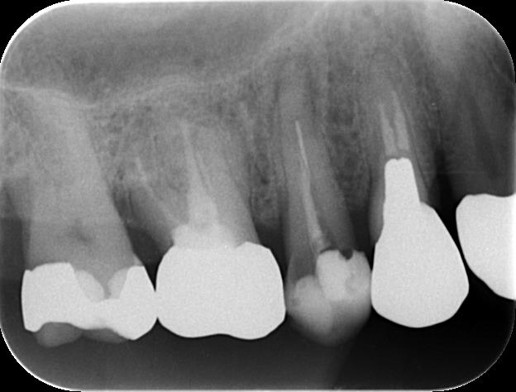

治療前 ![]() |

レントゲンで確認すると、ファイルが破折している可能性が確認できました。 |